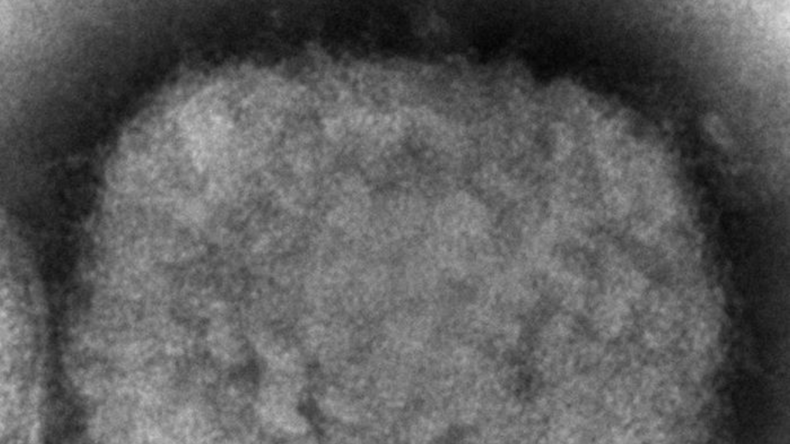

Image prise au microscope électronique en 2003, montrant un virion de la variole du singe (image d'illustration).© Cynthia S. Goldsmith, Russell Regner Source: AP

Image prise au microscope électronique en 2003, montrant un virion de la variole du singe (image d'illustration).